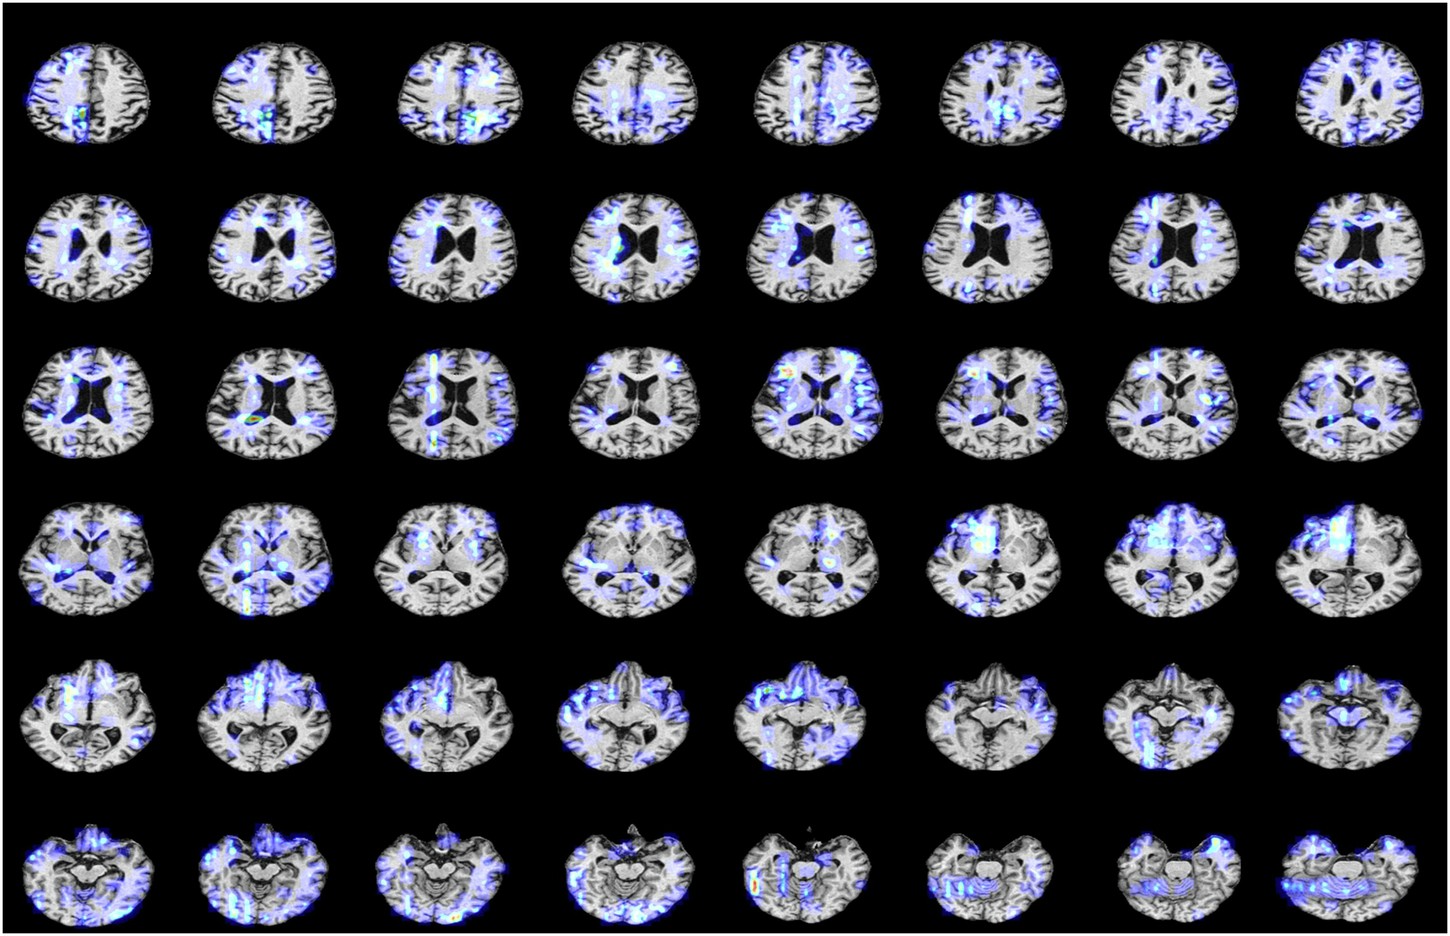

The continuous annotation performance for a single AD (Alzheimer’s Disease) patient.